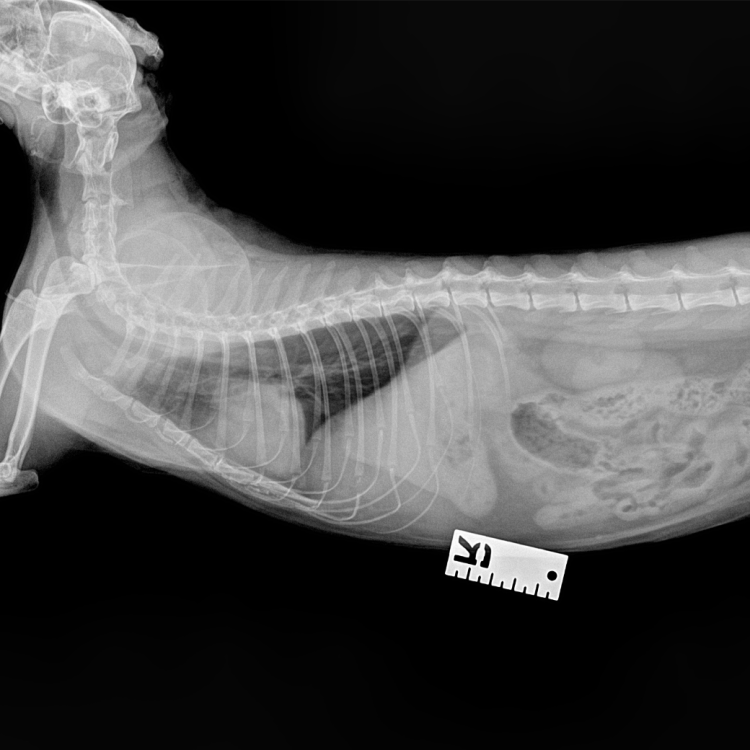

การตรวจเอกซ์เรย์ (X-Ray) เป็นการตรวจวินิจฉัยด้วยรังสี x โดยภาพที่ได้จะมีสีขาว - ดำ

ที่มีระดับความเข้มของสีที่แตกต่างกันขึ้นกับการดูดกลืนรังสีของแต่ละอวัยวะ

ตำแหน่งในการเอ็กเรย์ถูกแบ่งออกเป็น 3 ระบบหลักๆ คือ

การถ่ายภาพเอกซเรย์ (X-ray) ให้กับสัตว์ป่วย โดยทั่วไปไม่จำเป็นต้องเตรียมตัวพิเศษนัก ยกเว้นในบางกรณี เช่น การถ่ายภาพเอกซเรย์ข้อสะโพกที่สัตว์อาจเกิดความเจ็บปวด